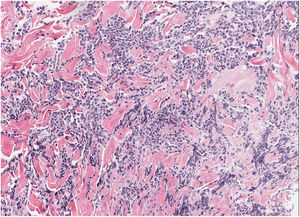

HistopatologíaLa biopsia cutánea reveló un denso infiltrado linfoide dérmico formado por células de tamaño intermedio con ocasionales células grandes, así como algún eosinófilo acompañante (fig. 2). Presencia de centros germinales y no confluentes en dermis profunda. Estudio inmunofenotípico: infiltrado mixto de células T (CD3+, CD4+, CD7+) CD30− con ocasionales células PD1+, y células B (CD20+, CD79a+) bcl2− con positividad focal para CD10 y CD21. No se observó restricción de cadenas ligeras de las inmunoglobulinas por hibridación in situ. Reordenamiento de los genes del receptor de células T y de las cadenas pesadas de las inmunoglobulinas: patrón policlonal.

El estudio histopatológico evidencia un infiltrado linfoide nodular, sin atipia celular, que afecta a toda la dermis, con formación de centros germinales grandes y confluentes con una zona del manto reducida o ausente. El infiltrado se compone por células plasmáticas, eosinófilos, linfocitos T reactivos y macrófagos con células apoptóticas fagocitadas en su interior (tingible bodies). El inmunofenotipo demuestra una proliferación linfoide con predominio de célula B del centro germinal, con positividad para CD20, CD10 y bcl-6 y negatividad para bcl-2, con expresión politípica de las cadenas ligeras de las inmunoglobulinas6.